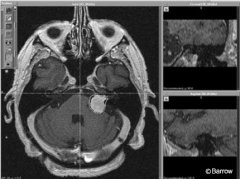

听神经瘤ct能查出来吗?如何切除

听神经瘤ct能查出来吗?计算机断层扫描在诊断听神经瘤中是有用...